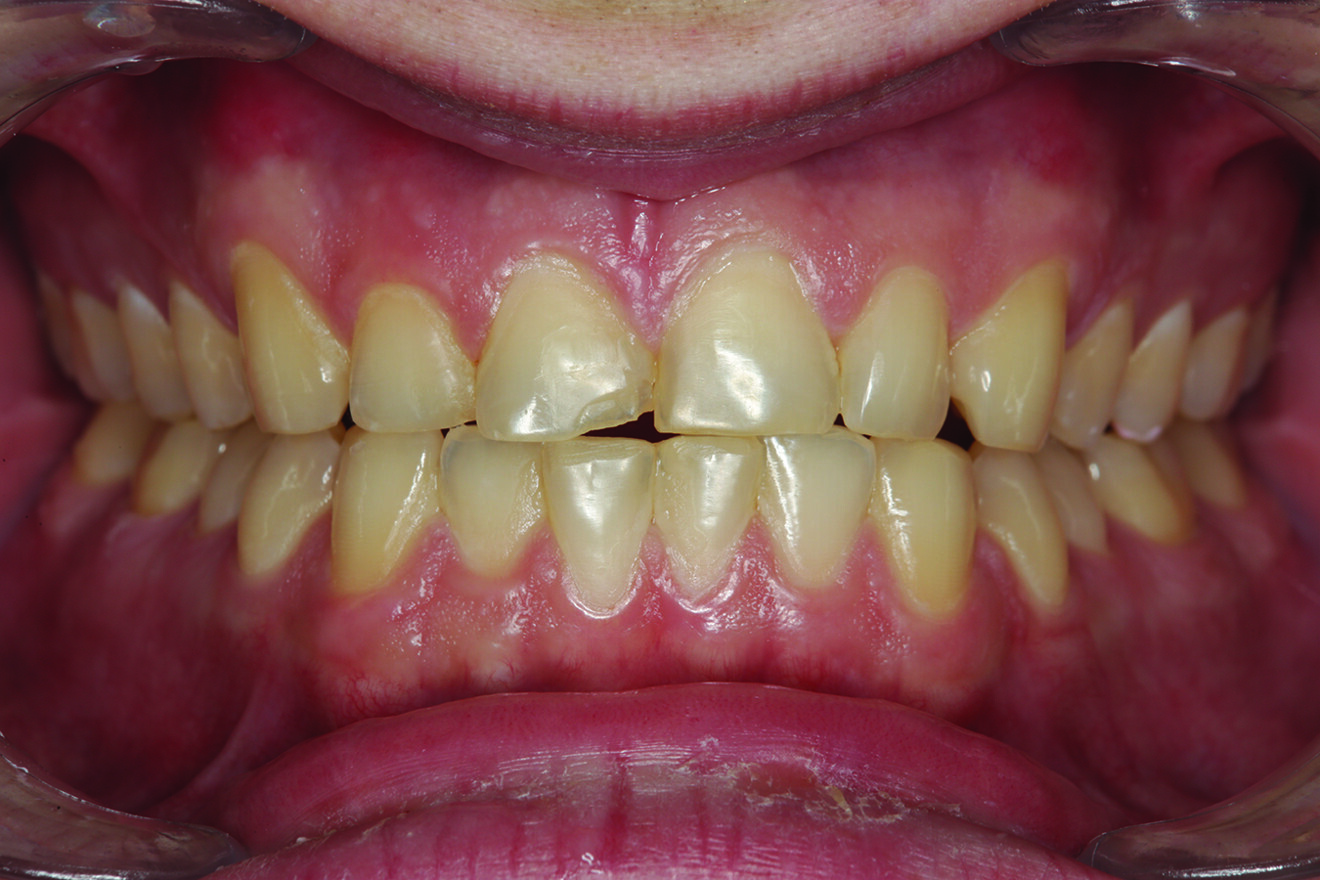

Fig. 1: Pre-op retracted facial view of the fractured composite restoration on tooth #11 with the teeth in maximum intercuspation. (All images: Robert A. Lowe)

The patient presented with a fractured Class IV mesial–incisal composite restoration on tooth #11 (Fig. 1). It had been repaired three times dur­ing the past year and had fractured again. Was this due to poor technique, maybe inferior materials? More than likely, it was due to occlusion. Aside from the amount of composite on the facial sur­face that extended beyond the fractured area, most of the palatal surface of the tooth was worn through to the dentine due to hyperfunction in protrusive and lateral excursion over many years, creating a functional and aes­thetic dilemma for the patient. A “conservative” approach may have been to bond the tooth again with composite and hope for the best. However, this may not have been the best long-term approach considering the functional stress in this area, even with the best tooth alignment. After all, how conservative is it to continually assault the tooth with rotary instrumentation to keep fixing a composite that continues to fracture?